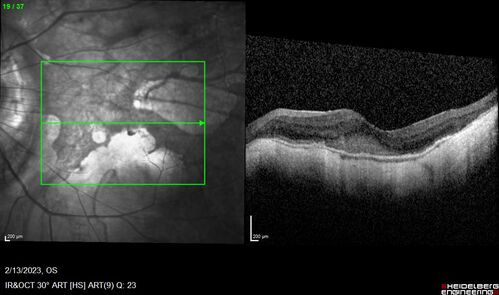

Myopic CNVM Left Eye

80 year old female. VA dropped to 20/125 but improved back up to 20/50 with Vabysmo